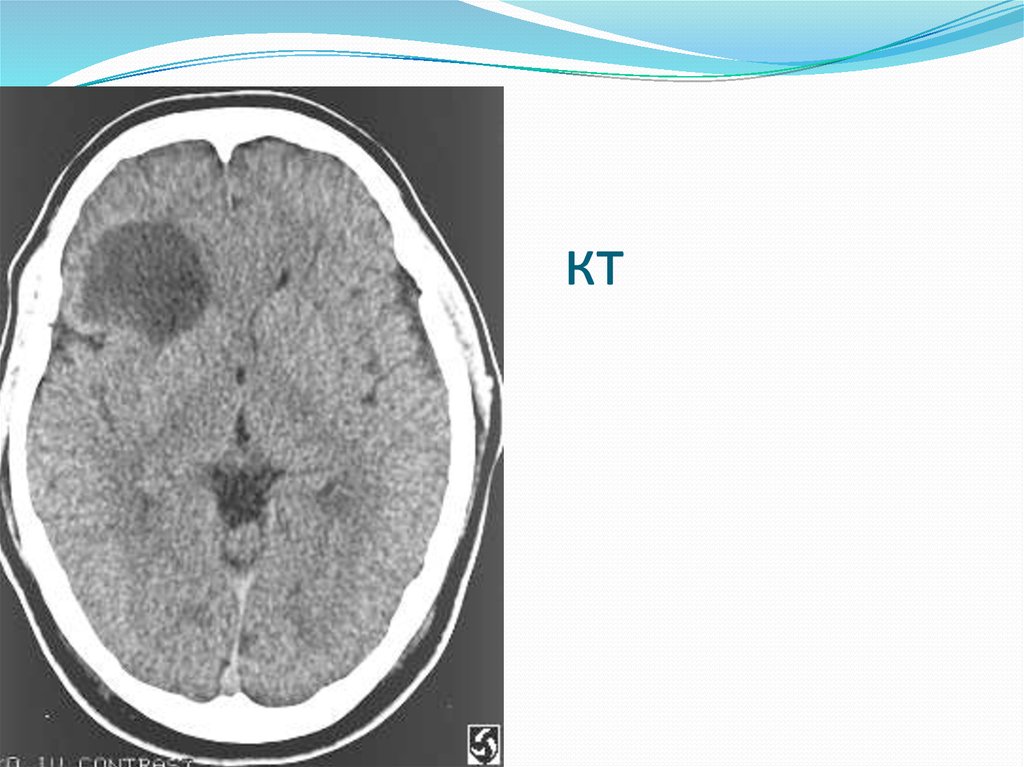

6. Менингиома

7. кт